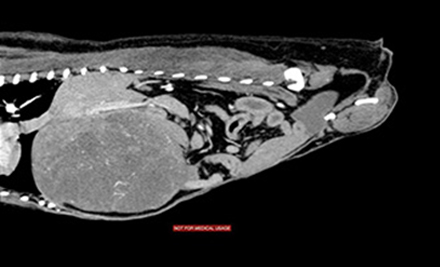

特に難しいと言われる肝臓腫瘍摘出には、CTを用いた綿密な術前計画、手術中も超音波吸引器、超音波メス、プリングル法、術中超音波検査を駆使して出血の少ない安全で適切な手術を心がけております。

術前CT画像

CT画像 CT画像